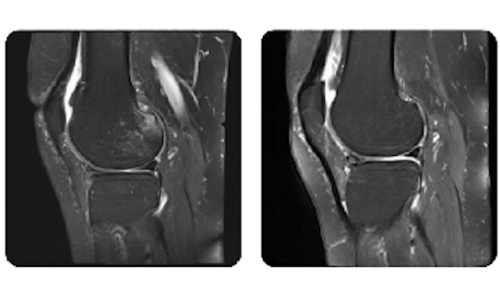

I progressi dei nostri pazienti, misurati prima e dopo la terapia iperbarica, riflettono l'efficacia e l'impatto positivo del trattamento. Scopri i risultati documentati della terapia iperbarica presso la clinica Hyperbarium Oradea, basati su valutazioni cliniche e dati oggettivi che evidenziano miglioramenti significativi in diverse condizioni.